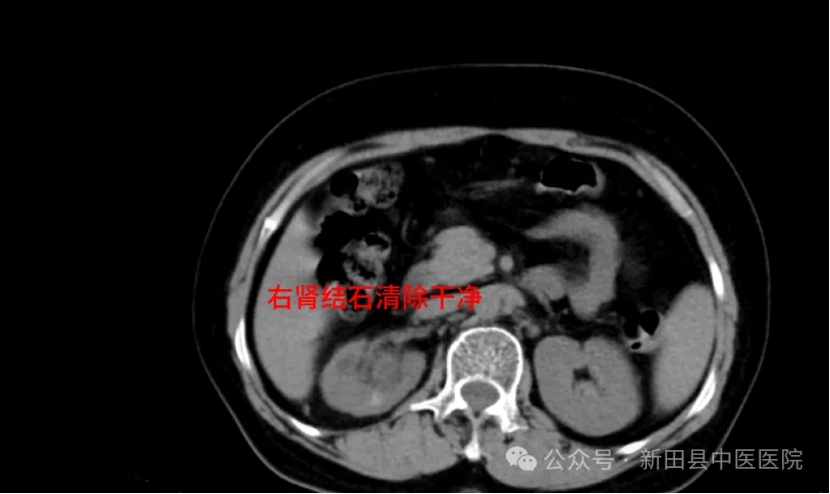

陈女士入院后,予积极完善相关检查。开展术前讨论,全面评估病情,制定手术方案。在做好充分术前准备后,邓勇军团队为陈女士施行了右侧经皮肾镜钬激光碎石取石术(PCNL术)。凭借丰富的经验和精湛的技术,邓勇军顺利将陈女士肾脏内的这颗“鹿角”成功击碎清除。

术后影像学检查提示,右肾结石清除干净。一周后,陈女士康复出院时,对邓勇军主任连声称赞。

▲术后CT